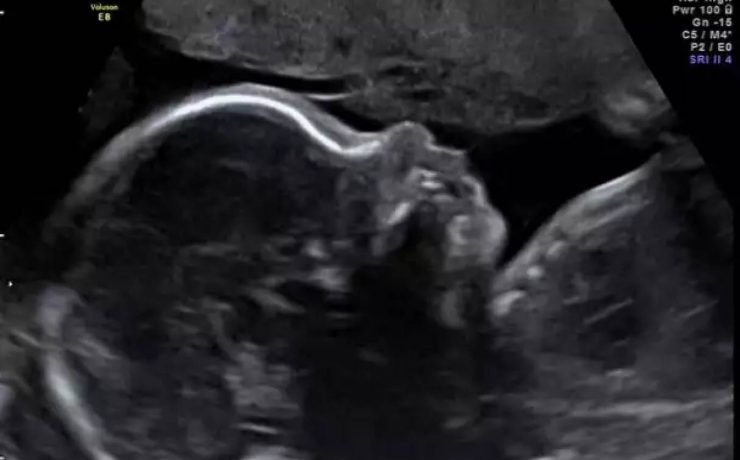

Onfalocele fetal

El onfalocele o exónfalo es un defecto en el desarrollo de la pared abdominal, en el que las vísceras herniadas están cubiertas por peritoneo, amnios y gelatina de Wharton. Los órganos comprometidos en la evisceración pueden ser asas de intestino delgado o grueso, hígado y estómago, estando siempre incluido el